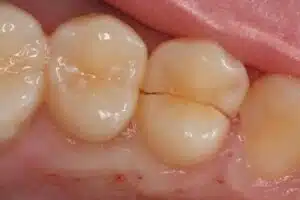

More people are keeping their natural teeth for life, which is good news for smiles—but it also means we are seeing more teeth develop structural problems over time. Heavy biting forces, large fillings, root canal treatments, and day-to-day stress can all weaken a tooth and set the stage for what dentists call a cracked tooth. In fact, cracked tooth problems are now one of the more common reasons adults report mystery biting pain.

Not all cracks are equal. Tiny craze lines in the enamel are extremely common and are usually harmless. Deeper cracks that extend into the dentin, or all the way into the pulp, are more concerning:

- Shallow structural cracks may cause biting sensitivity but can often be stabilized with an onlay or crown.